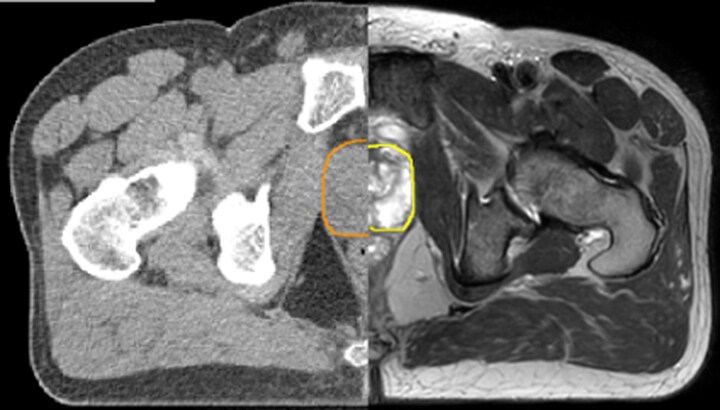

With its exceptional soft-tissue visualization capabilities and wide range of image contrasts, MRI has become a powerful tool to help more precisely define tumor boundaries. This is particularly important as it has been established that there is a high degree of uncertainty in target volume delineation, and it is even reported to represent the largest uncertainty in the entire radiotherapy process for most tumor sites**. Better visualization of the target area and nearby organs-at-risk is a key factor in enhancing target volume delineation. MRI’s expanding role also can be attributed to its functional imaging capabilities, which can inform both target characterization and treatment response.

With its superior soft tissue contrast compared to CT, MRI offers exquisite visualization of tumor boundaries and proximity to nearby critical structures.

Diffusion-weighted imaging (DWI) for example depicts areas of high signal intensity in soft tissues that are indicative of the restricted water mobility (i.e., diffusion) of a tumor and can also be used to identify lymph nodes. Changes in the tissue’s or lesion’s apparent diffusion coefficient (ADC) can provide insights that help predict the tumor’s response to radiotherapy.